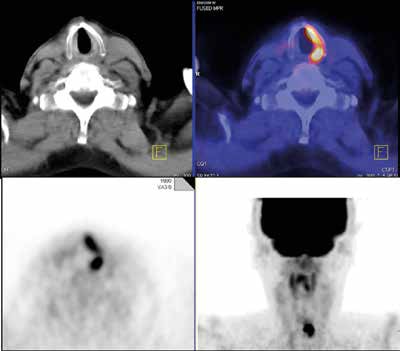

This clinical case shows a potential false-positive interpretation. A 70-year-old man with thyroid cancer and multiple past surgeries underwent restaging because of rising tumor marker. FDG-PET/CT showed asymmetric strong FDG uptake in the left vocal cord due to right recurrent laryngeal nerve palsy from prior surgery and tumor involvement. The compensatory activation of the nonparalyzed left vocal cord showing increased FDG uptake should not be misinterpreted as malignancy. Image courtesy of Dr. Christina Pfannenberg.There are several sites of normal physiologic uptake of FDG -- most intense in the cerebral cortex and less intense in the myocardium, liver, kidneys, and bone marrow. The uptake can be highly variable in the lymphatic tissue, salivary glands, thymus, muscles, ovary, testes, activated brown fat, and the gastrointestinal tract. One of the most important challenges is to correctly differentiate physiological uptake from these normal variants, and this differentiation can prove a great source of potential false-positive interpretation.